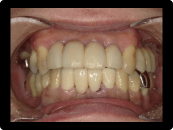

歯周病の治療例

奥歯の重度歯周病は保存困難のため抜歯してインプラント治療。残す歯は歯周病中等度であったため、歯周基本治療歯周外科治療を含めて行い、歯茎からの出血などはなくなった。

BEFORE

AFTER

症例概要

年代・性別

50代 女性

主訴

全体の歯茎から出血する、奥歯が揺れて噛めないことを主訴に来院されました。

治療内容

全顎歯周外科治療(保険治療)+奥歯インプラント治療4本

治療期間

6ヶ月

治療のリスク

歯肉退縮のリスクがあります

治療費用

約160万円